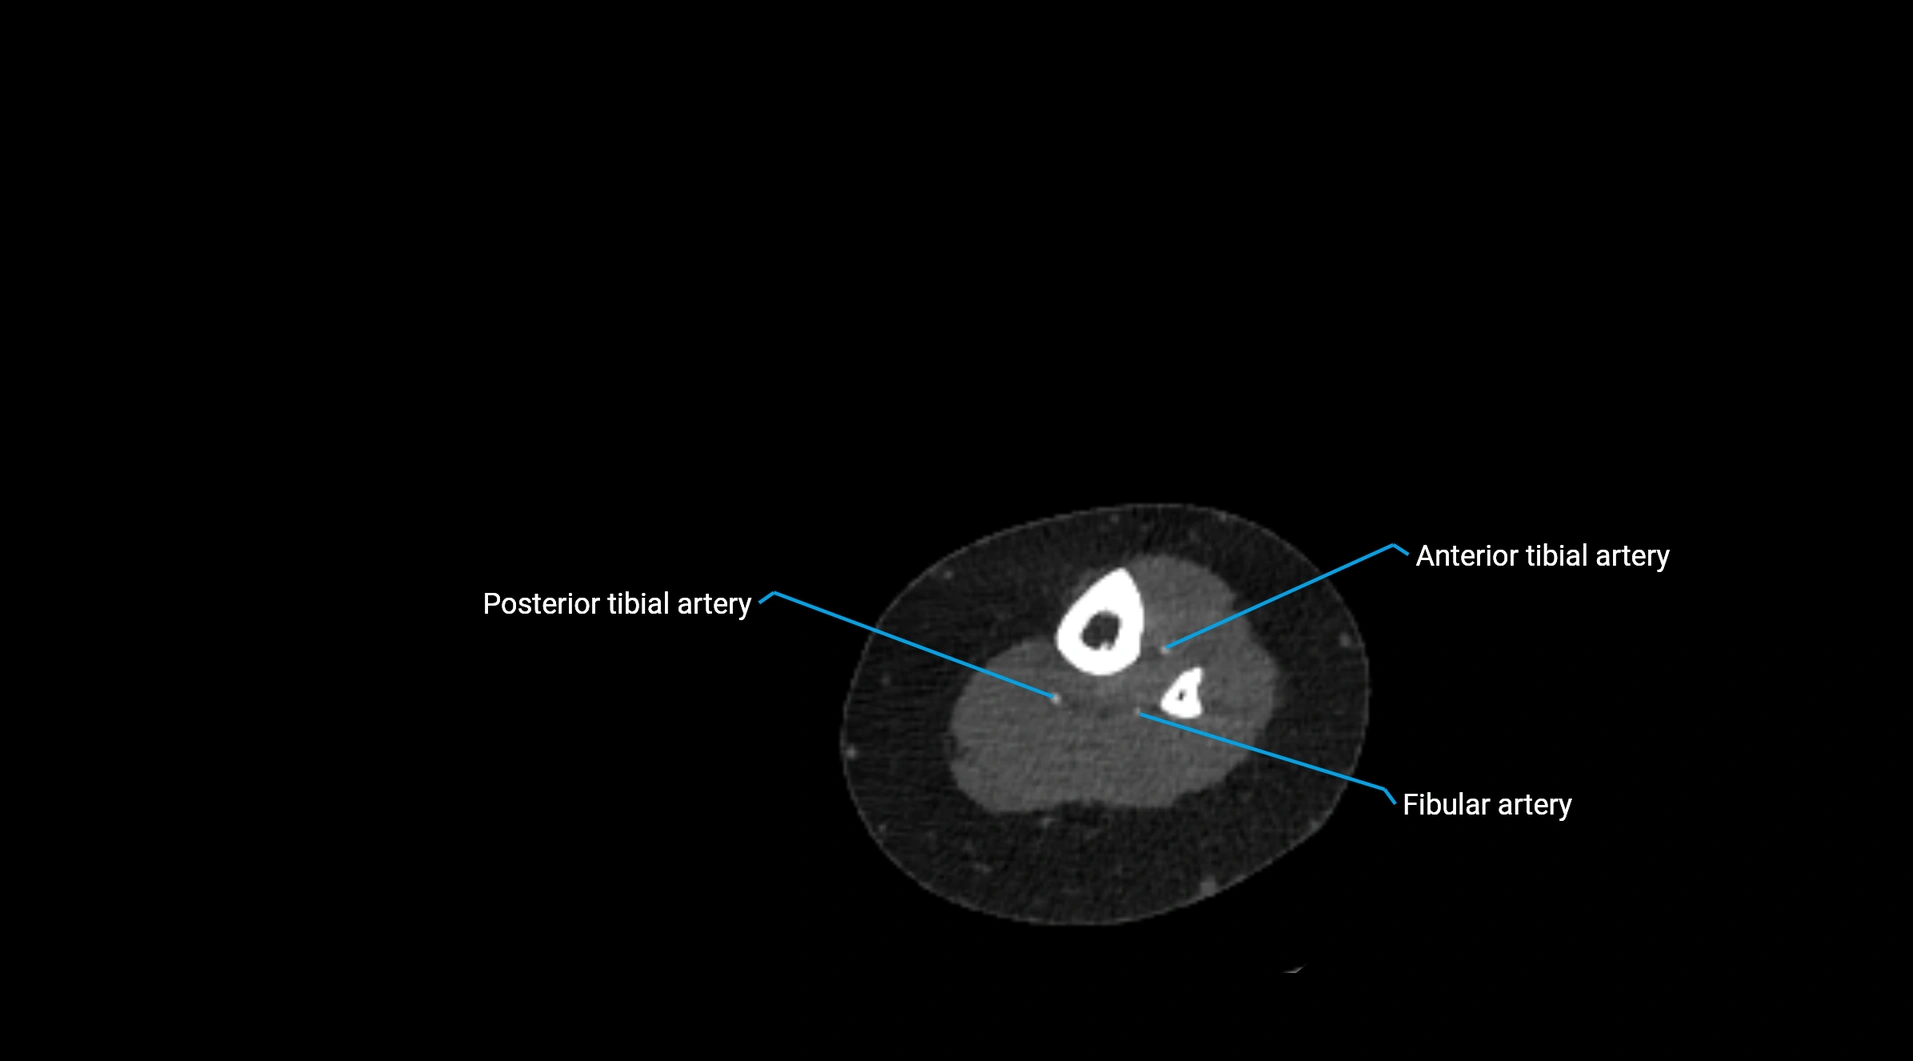

CT images

image

Contrast-enhanced CT (CTA):

• Gold standard for abdominal aortic imaging

• Provides excellent detail of lumen, wall, aneurysm, thrombus, and branch vessels

• Multiplanar and 3D reconstructions help in aneurysm measurement, stent graft planning, and dissection evaluation

• Detects acute rupture, traumatic injury, or occlusion with high sensitivity